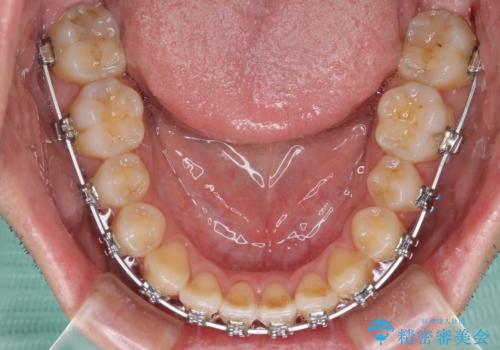

左右の八重歯が気になる ワイヤー装置での咬み合わせ改善

- メタルブラケット

舌の突出癖がなかなか改善されず、上下前歯部の接触が得られるまでに予定の倍ほどの期間がかかりました。

- 4年1ヶ月